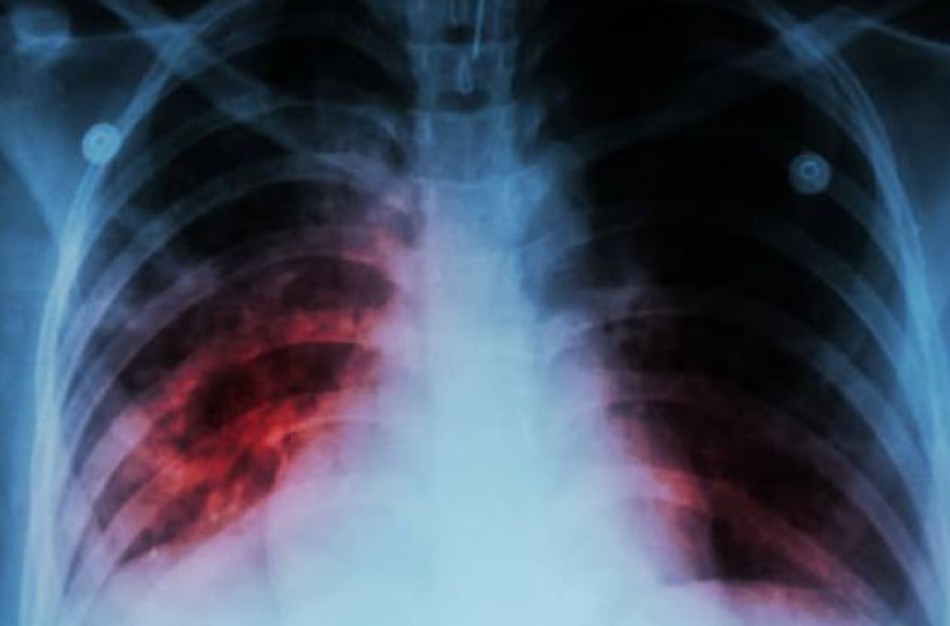

ULAC medikai primena, kad TB infekcijos šaltinis yra atvira plaučių TB sergantys ligoniai, pastarieji kosėdami, čiaudėdami ir skrepliuodami į aplinką išskiria gausų kiekį ligos sukėlėjų – tuberkuliozės mikobakterijų. Ši liga ypač grėsminga naujagimiams, kūdikiams ir vaikams iki 5 metų.